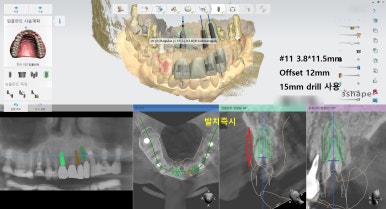

네비게이션 임플란트를 사용하여 적절한 간격과 각도를 유지하였고

특히 앞니의 경우 뼈가 매우 얇았으나 내비게이션을 사용하여

뼈가 얇아도 뼈를 뚫고 나갈 위험이 없이 적절한 뼈 위치에 임플란트를 식립하였습니다.